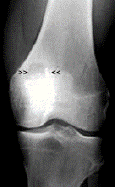

Chondroblastoma

rare, benign neoplasm occurring second decade when growth plates are still open

70% in proximal humerus and knee, invariably at EPIPHYSIS

irregular but circumscribed, radiolucent epiphyseal lesion surrounded by reactive bone sclerosis